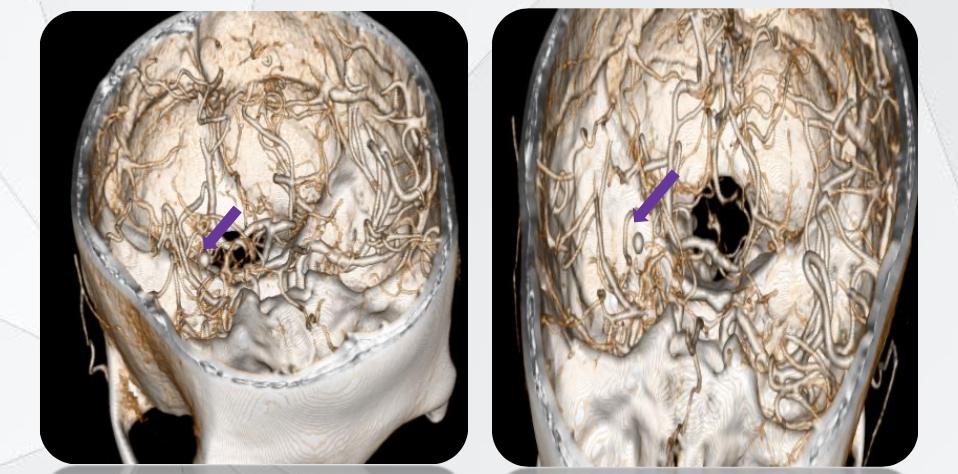

以中创五联的实际服务的“偏头痛”病案为例。临床时医生常以“少激动、多休息”为医嘱并辅以内科治疗,而中创五联通过分析患者头部CTA与MRI图像,进行多维滤波优化、多模态深度配准与融合重建,通过精准的三维模型,展现了患者偏头痛的病因是由于小脑动脉(基于CTA重建)挤压邻近三叉神经(基于MRI重建)所致,医生通过观察模型,获得了准确、可视的诊断与术前评估信息,使用微创手术帮助患者结束了持续了两年多的偏头痛,使患者生活质量显著提高。